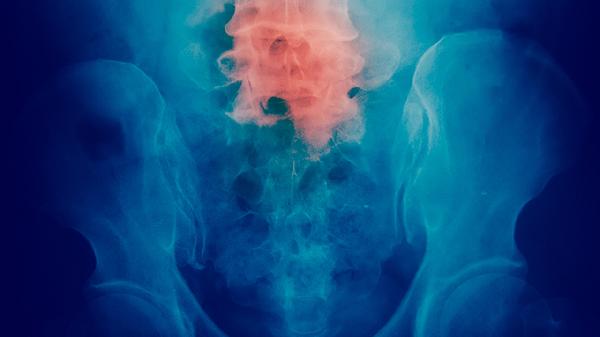

胸痛多表现为胸部隐痛或钝痛,位置常与肿瘤部位相对应。早期胸痛多为间断性,咳嗽或深呼吸时可能加重。胸痛与肿瘤侵犯胸膜或胸壁有关,随着肿瘤增大可能出现持续性疼痛。